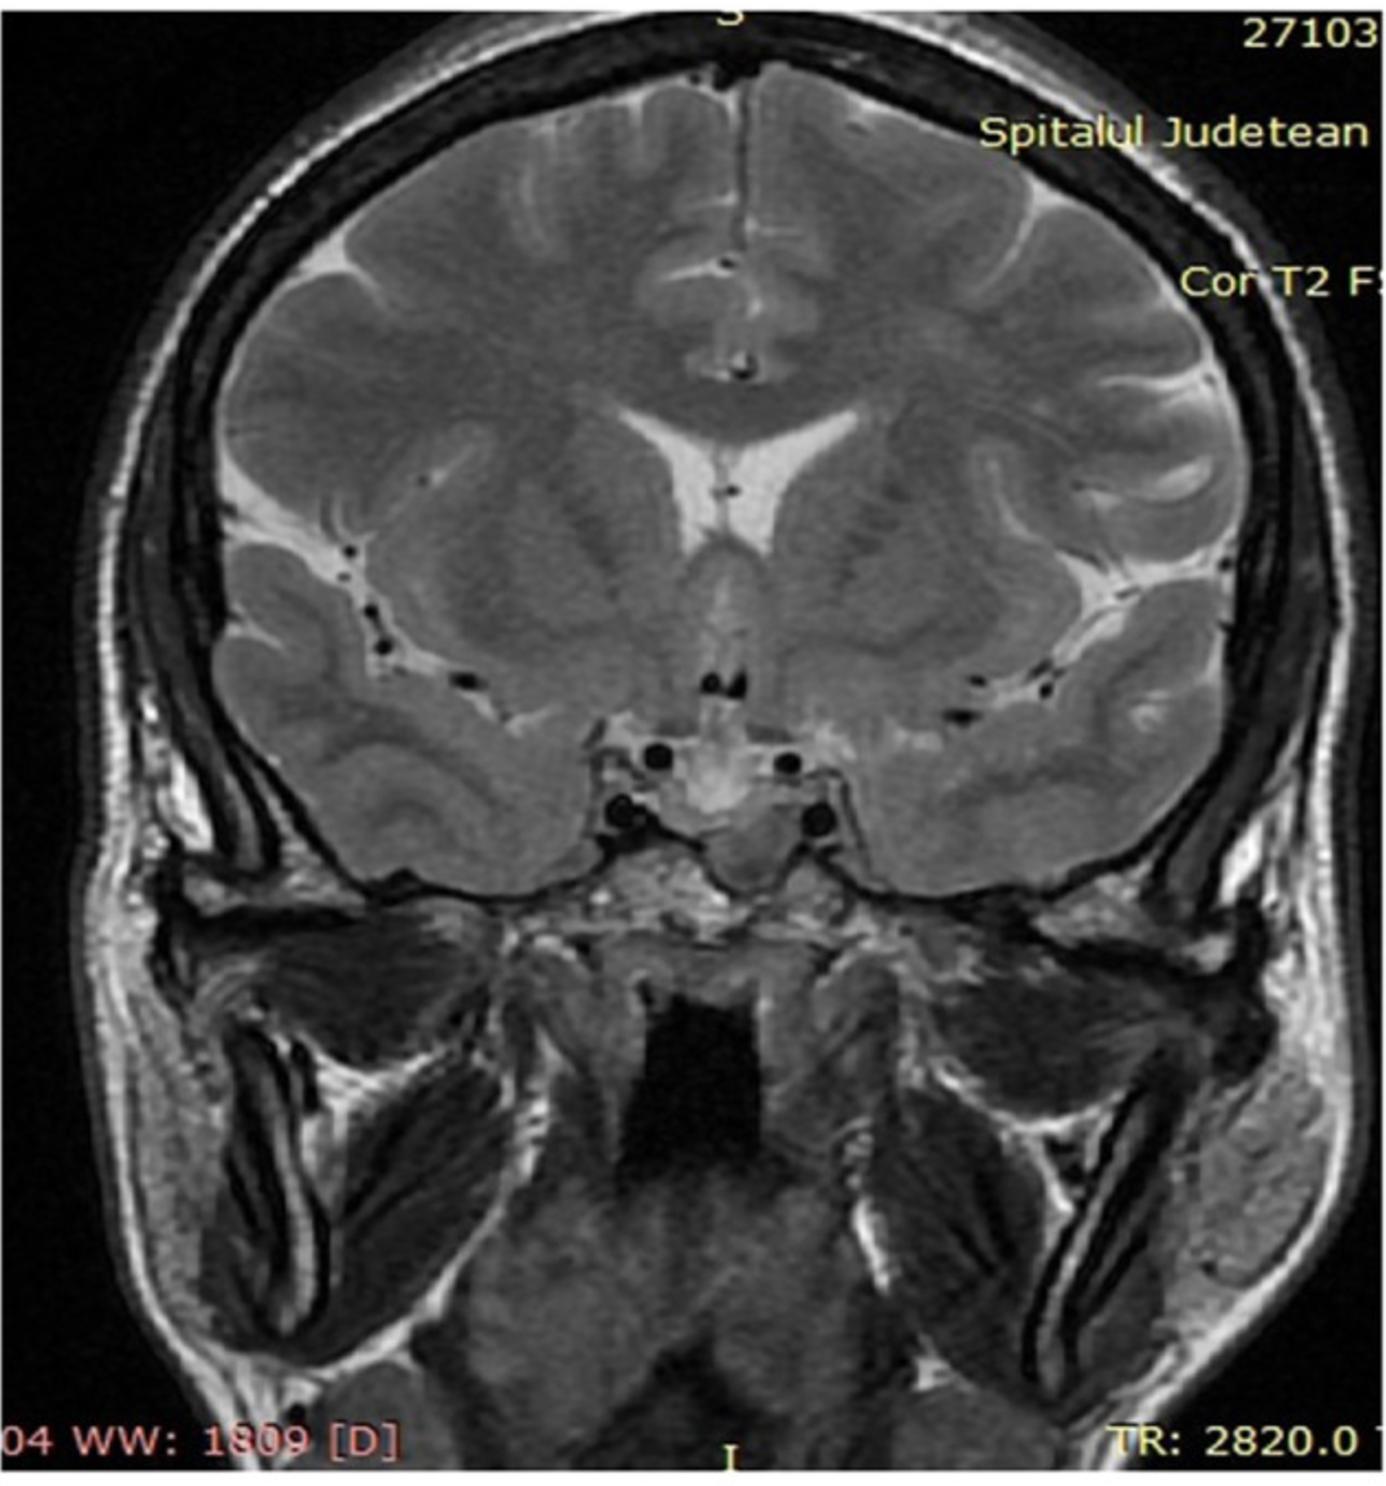

随后进行了更详细的病史和有针对性的临床检查。查体见:大舌苔、齿间隙增加(图4A)、嘴唇增厚和鼻唇沟突出(图4B)。患者还提到,她有大约5年没能摘下结婚戒指。随后怀疑肢端肥大症,因此测定了IGF-1(891 ng/ml,年龄和性别的正常范围83.3-220 ng/ml)和基础生长激素(20.2 ng/ml,性别和年龄的正常值<10 ng/ml)。还进行了口服75g葡萄糖的抑制试验,显示GH抑制在1ng/ml以下失败,从而证实了肢端肥大症的诊断。对垂体整体功能的评估没有发现其他激素缺乏(催乳素=4 ng/ml,正常范围2.8-29.2 ng/ml;FSH=75.98 mIU/ml,更年期正常范围23-1016.3 mIU/ml;LH=43.05 mIU/ml,更年期正常范围7.9-53.8 mIU/ml);雌二醇<11.80 pg/ml,更年期异常范围<32.2 pg/ml;皮质醇=12.38 mcg/dl,正常范围=4.3-22.4 mcg/dl)。进行垂体MRI发现大腺瘤(13/9mm),与正常垂体实质相比(T2加权信号)强度较低,侵入左侧蝶窦,没有压迫视交叉(图5)。

图5 MRI,冠状位,T2,侵犯左侧蝶窦的13/9mm低强度腺瘤